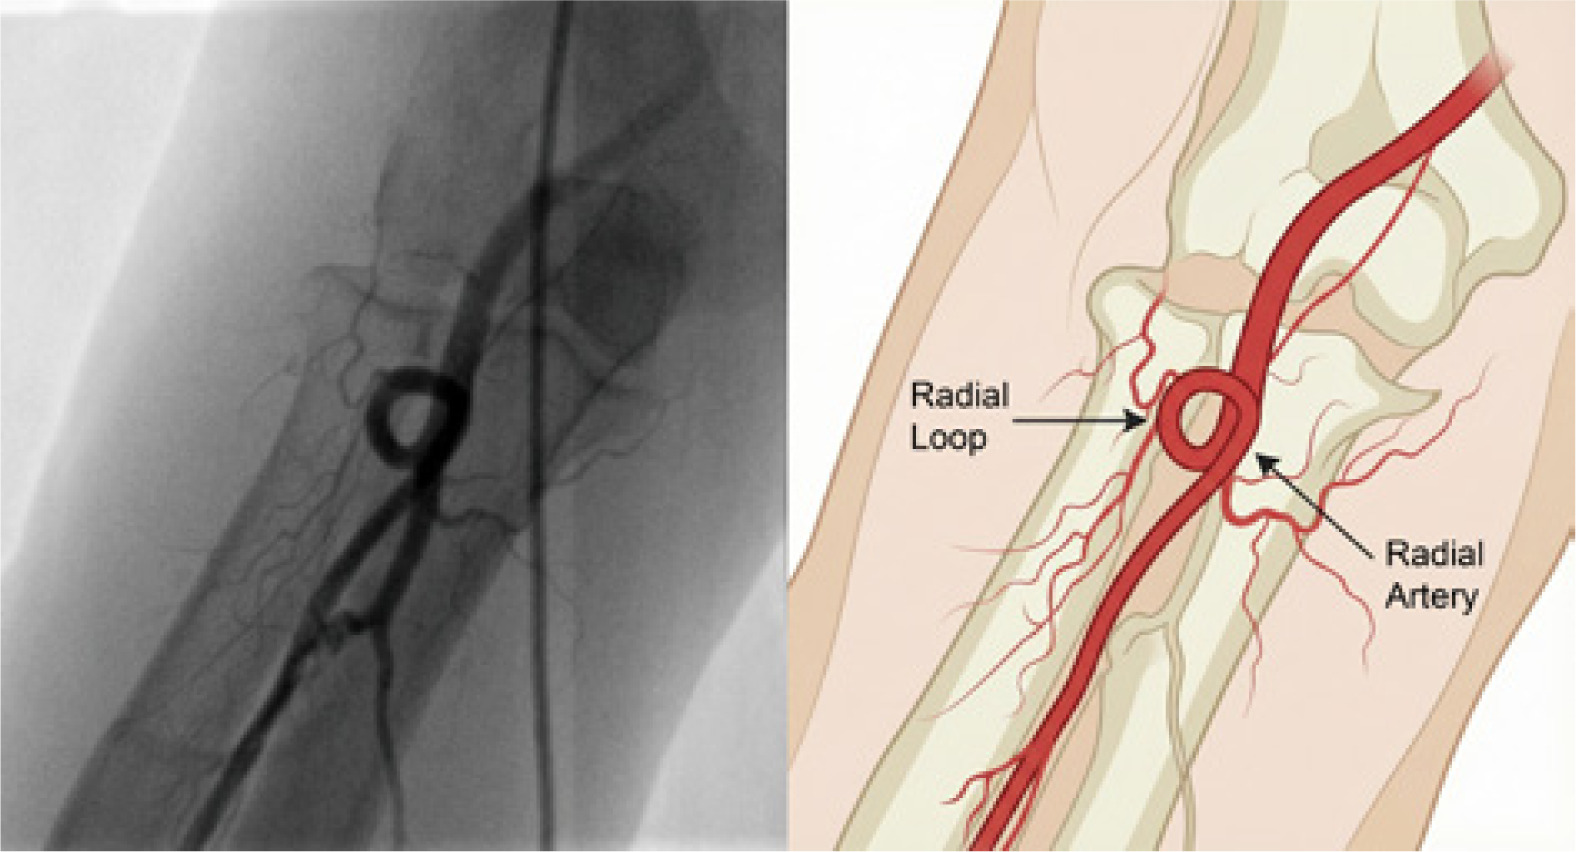

These variants encompass not only differences in origin but also altered courses and relationships to surrounding neurovascular structures. Another notable variant is the RA loop (Figure 2), which can complicate wire advancement and increase the risk of vessel trauma [13].

Figure 2

Radial artery loop during transradial catheterization: angiographic appearance (left) and anatomical illustration (right)